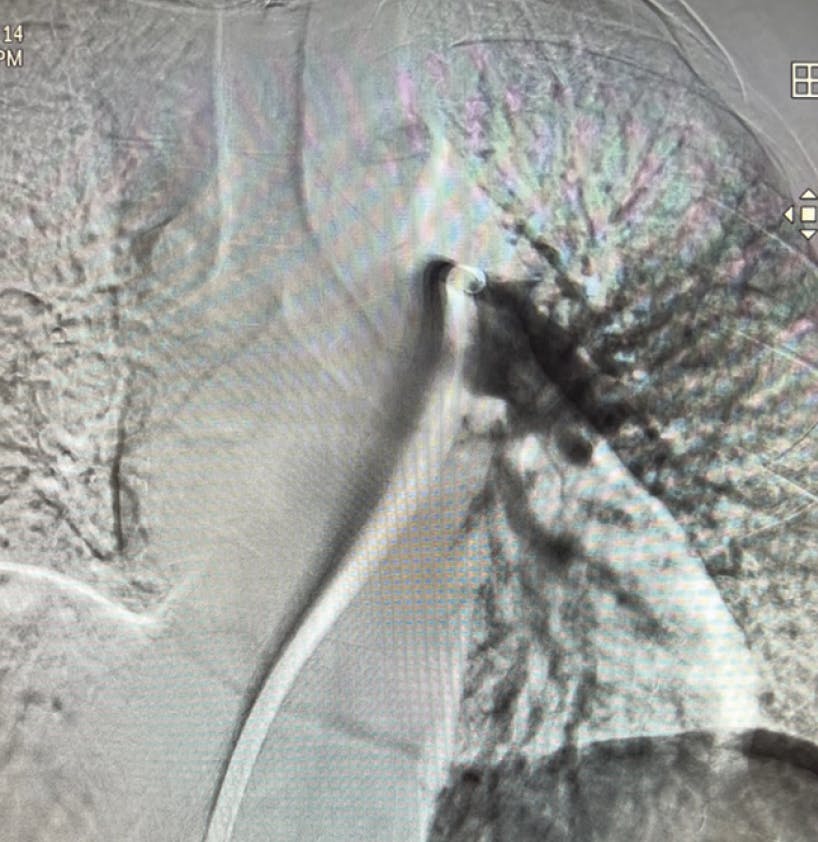

Based on evaluation, we decided to pursue aspiration thrombectomy utilizing Lightning Flash through a 16-F, 65-cm Gore DrySeal sheath (Gore & Associates). We achieved access in the right femoral vein. The device time was 17 minutes, and the total procedure time was 30 minutes (Figure 3, Figure 4, Figure 5, and Figure 6). At the conclusion of the case, the total EBL was 175 mL, the patient had BP of 112/67 mm Hg, HR of 65 bpm, and oxygen saturation of 99% on 3 L nasal cannula.

Figure 3. Post-thrombectomy lower right lobe angiogram.

Figure 4. Post-thrombectomy upper right lobe angiogram.

Figure 5. Post-thrombectomy left lobe angiogram.

INTERVENTION

Based on the evaluation, the decision was made to pursue aspiration thrombectomy using the Lightning Flash device. The opening PA pressures were 33/12 mm Hg (mean, 20 mm Hg) and closed with 18/3 mm Hg (mean, 8 mm Hg), taken through the 16-F, 65-cm Gore DrySeal sheath, showing a significant drop in pressure. The device time of Lightning Flash was 6 minutes, and the total procedure time was 55 minutes (Figure 3, Figure 4, and Figure 5). By the conclusion of the case, the EBL was 100 mL and postprocedure BP was 122/63 mm Hg, HR was 54 bpm, and oxygen saturation was 97% on 2 L nasal cannula.

Figure 3. Right post-thrombectomy angiogram.

Figure 4. Left post-thrombectomy angiogram.

After initial evaluation, the decision was made to use aspiration thrombectomy to remove the PE thrombus. We utilized a 16-F, 65-cm Gore DrySeal sheath through the right femoral vein. Penumbra’s Lightning Flash was used for a device time of 10 minutes (Figure 3, Figure 4, and Figure 5). The total procedure time was only 20 minutes. With the conclusion of the case, we had an EBL of 120 mL and a postprocedure BP of 120/87 mm Hg. The HR decreased substantially to 98 bpm, and the oxygen saturation improved to 100% on room air.